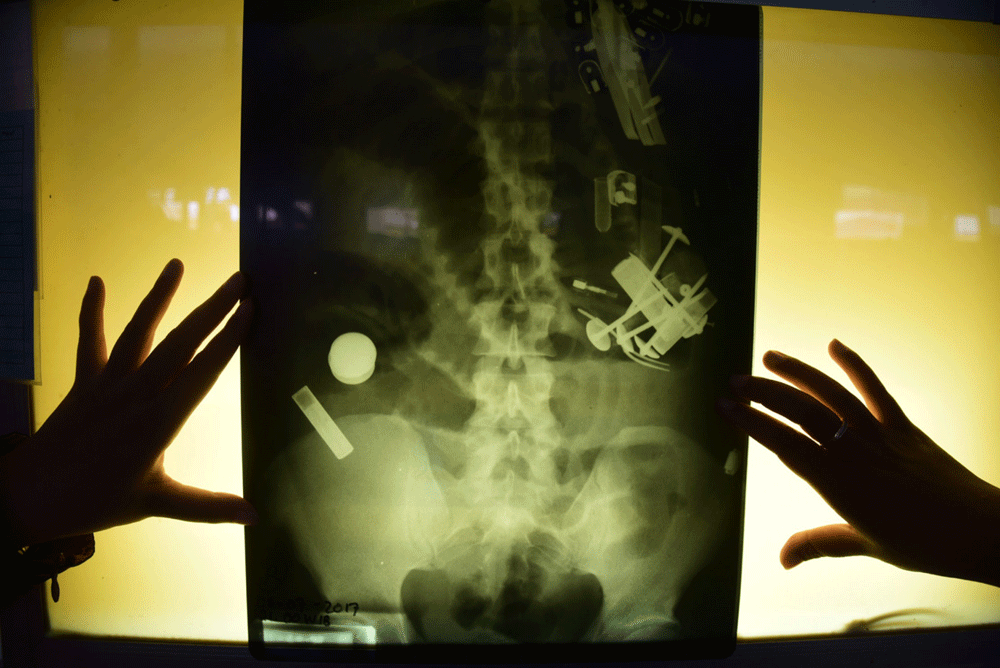

Tapi, hasil rontgen dokter di Rumah Sakit Umum Daerah (RSUD) Abdoer Rahem, Situbondo, Kamis (6/7) lalu membuat pria 37 tahun itu terbelalak. Dalam perut Hendro ternyata ditemukan sejumlah paku payung ukuran besar, pinset (pisau kecil), sendok, bahkan korek api.

Dosen Fakultas Kedokteran Universitas Jember yang juga spesialis penyakit dalam dr Yuli Hermansyah SpPD Finasim menambahkan, kalau melihat sekilas dari foto rontgen RSUD Situbondo yang beredar di media, berbagai benda tersebut sudah masuk usus. Mungkin di usus 12 jari atau usus besar.

”Dengan kondisi itu, memang kemungkinan besar benda-benda seperti paku, paku payung, dan bentuk pisau itu masuk melalui oral alias mulut,” katanya.

RSD dr Soebandi belum menentukan tim dokter yang akan menangani Hendro. Tapi, menurut Yuli, untuk mengambil berbagai benda di perut bujangan dari Panarukan itu, harus dilakukan operasi.

Memang ada alternatif endoskopi via oral alias mulut jika posisi benda di usus 12 jari. Atau melalui anus di posisi paku dan lain-lain itu di usus besar.

Cuma, yang bisa diambil alat endoskopi tidak terlalu besar. Juga tidak sebanyak yang terjadi pada Hendro.

”Yang ini harus dengan operasi,” tegas dia. (KHAWAS AUSKARNI, Jember)